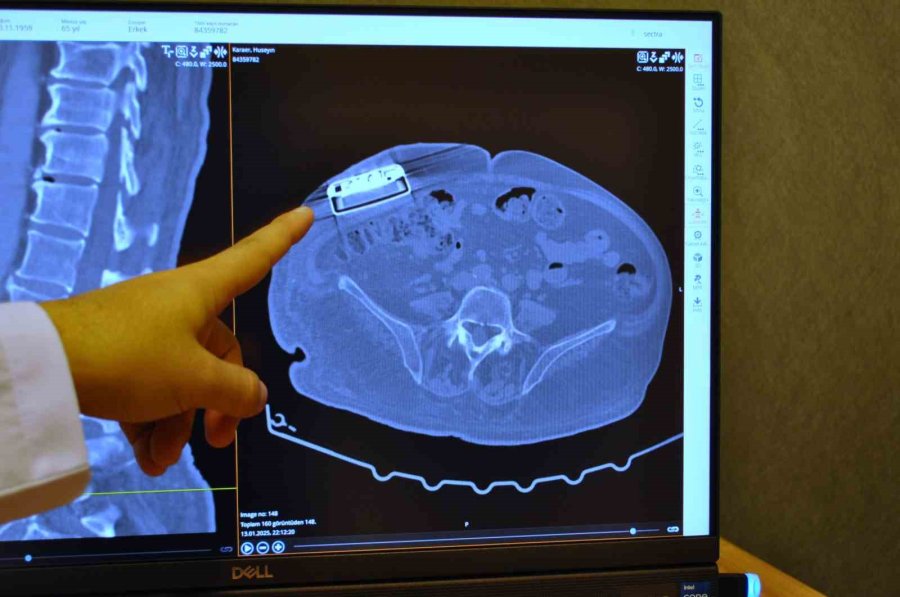

Geçirdiği trafik kazası sonucunda omuriliğinde hasar oluşan ve yaklaşık 11 sene önce kendisine baklofen pompası implante edilen 65 yaşındaki erkek hasta, cihazın değiştirilmesi için Acıbadem Eskişehir Hastanesi müracaat etti. Beyin ve Sinir Cerrahı Uzmanı Dr. Beşir Sürme tarafından hastaya pompa değişimi ameliyatı yapıldı. Operasyon sonucunda, hastaya gelişmiş yeni teknoloji baklofen pompası yerleştirildi. Baklofen pompalarının kullanımının çok yeni olmasa da, bahse konu olan yeni teknolojinin ülkemizde ilk kez kullanıldığı belirtildi.

Operasyonla ilgili açıklamalarda bulunan Beyin ve Sinir Cerrahı Dr. Beşir Sürme, "65 yaşında erkek hasta, trafik kazasına bağlı bir omurilik hasarı geçiriyor ve bunun akabinde parapleji dediğimiz güç kaybı meydana geliyor. Gelişen bu omurilik hasarına bağlı hastada spastisite dediğimiz şiddetli kasılmalar oluşuyor ve hastaya baklofen pompası denilen bir cihaz implante ediliyor. Yaklaşık 11 sene önce implante edilen bu pompanın miadının dolması üzerine bize başvurdu ve biz bu hastamızda bir pompa değişimi ameliyatı gerçekleştirdik. Baklofen pompası tedavisi Türkiye'de daha önce de yapılan bir tedavi ancak biz yeni versiyon bir pompa yerleştirdik ve yeni özellikleri nedeniyle hastaya sağladığı özellikleri de gözlemledik" dedi.

Pompa tedavisinin daha önce uygulandığını ancak yeni teknoloji pompayı ilk kez erkek hastada kullandıklarını söyleyen Dr. Sürme, "Hastamızı yaklaşık 2 ay önce ameliyat ettik. Ameliyat sonrası programlamalarını yaptık. Bu hastalarda, hastalığın durumu ve hastanın ihtiyaçlarına göre verilecek ilacı pompa sayesinde programlayabiliyoruz. Programlamalardan sonra hastamız daha iyi olduğunu ve kasılmalarında belirgin düzelmeler olduğunu söylüyor. Hatta daha önceki pompaya göre şu an daha düşük doz ilaç vermemize rağmen hasta yine bundan fayda görebiliyor" şeklinde konuştu.